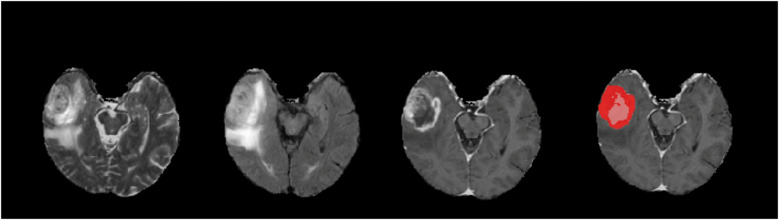

Methods: We trained a 3D U-Net DL model using the annotated 2018 MICCAI BraTS dataset (training dataset, n = 285), focusing on sub-segmenting enhancing tumor (ET) and tumor core (TC). We compared the performances of models trained on four different combinations of MRI sequences: T1C-only, FLAIR-only, T1C + FLAIR and T1 + T2 + T1C + FLAIR to evaluate whether a smaller MRI data subset could achieve comparable performance. We evaluated the performance on the four different sequence combinations using 5-fold cross-validation on the training dataset, then on our test dataset (n = 358) consisting of samples from a separately held-out 2018 BraTS validation set (n = 66) and 2021 BraTS datasets (n = 292). Dice scores on both cross-validation and test datasets were assessed to measure model performance.